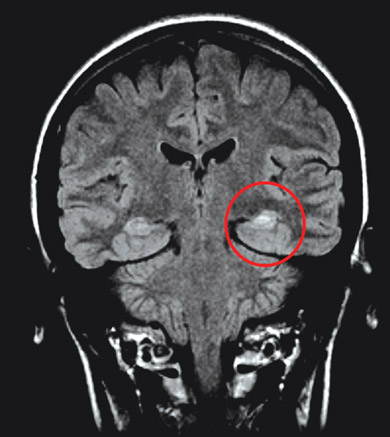

Neuroimaging: Nearly all adult patients with newly diagnosed focal seizures should undergo neuroimaging to assess for structural lesions of the brain, such as cerebral tumours, arteriovenous malformations, or scarring of the temporal lobe (hippocampal sclerosis). Magnetic resonance imaging (MRI) is the modality of choice, as it is superior to computed tomography in demonstrating subtle tissue changes such as those associated with an old ischaemic insult.4 However, it is essential that any structural findings are interpreted with caution and correlated with the clinical seizure characteristics and EEG findings, as structural lesions may be incidental (eg, diffuse white matter disease, lacunar infarcts, calcification, vascular spaces). Functional imaging modalities (such as positron emission tomography and single-photon emission computed tomography) can be used to evaluate patients who have medically refractory epilepsy and are being considered for surgical treatment, as these may provide additional localising information. Imaging may not be appropriate in children with typical benign focal syndromes, such as benign rolandic epilepsy and occipital epilepsy.

Hippocampal sclerosis is the most commonly identified pathological lesion in mesial temporal lobe epilepsy. A history of febrile seizures in infancy may be a marker of the condition in a minority of patients, such as Janice. Whether hippocampal sclerosis is a cause or an effect of seizures is uncertain.2